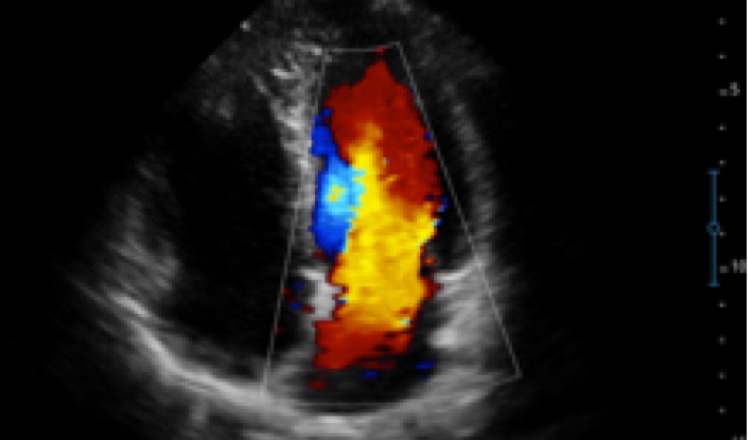

X5采用前端的超声专用芯片,将台式机大规模集成电路完美压缩在笔记本超声的精巧下,提高了系统的运算速度,加载μ-Scan微米成像、脉冲反相谐波等技术,带来优异的临床表现,清晰呈现高分辨率二维图像和层次丰富的血流图像

X5具备实时宽景成像、穿刺增强、彩色M型、组织多普勒等多种高级成像功能,全方位满足多个科室的诊断需求,整机系统向智能化跨越